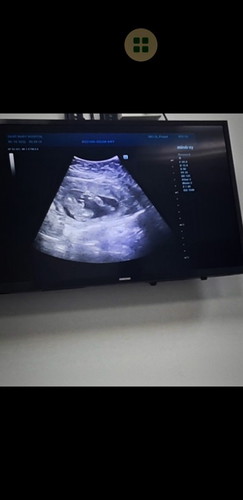

อัตเดตน้องค่ะแม่ๆ วันนี้หมอนัดตรวจอัลตร้าซาวด์ อายุครรภ์ตอนนี้ 10w3d ค่ะ เห็นน้องแล้วค่ะ ตอนตรวจอายุครรภ์ 7w4d ความยาวน้อง 1.31cm ปัจจุบันน้อง 3.57 cm ค่ะ หมอบอกหัวใจน้องเต้นแล้วปกติ น้องกำลังหลับอยู่🥰😁 #ใบอัลตร้าซาวด์แม่ๆบางคนเห็นตัวน้องชัดแจ๋วเลยของเราเป็นเพราะหนังท้องหนาหรือเครื่องตรวจคุณหมอหรือเปล่าคะ😅